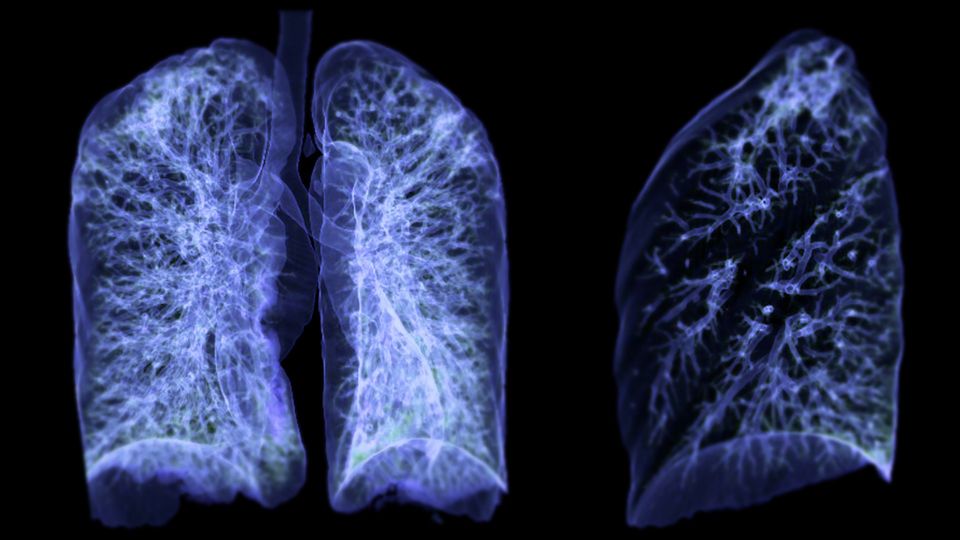

By creating high-resolution cellular and molecular visual maps of lung cancer before and during development, researchers at The University of Texas MD Anderson Cancer Center have discovered that the earliest stages of lung cancer may be driven by inflammation, suggesting that targeting proinflammatory pathways could be an early intervention approach.

Spatial transcriptomic maps provide a visual representation of where and how genes are expressed within samples. Characterizing the cells and genes in precursor lesions – early-stage growths or changes in tissues that have the potential to develop into cancer – can identify potential targets for early intervention.

The researchers generated spatial transcriptomic maps of 56 human precursor lesions and advanced lung cancer samples from 25 patients. They validated their findings using an independent cohort of 36 lesions from 19 patients, providing 486,519 spots and 5.4 million cells for analysis.